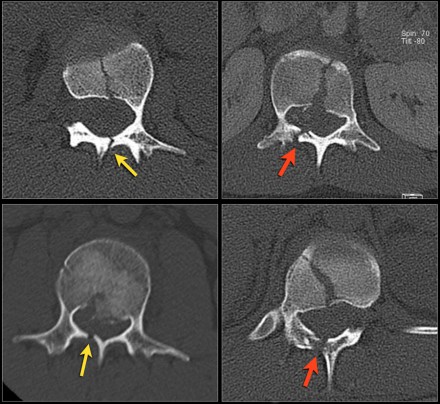

Look at the images.

What are the findings?

The findings are:

- Vertebral bodies show marrow edema as a result of a fracture.

- Torn flaval ligament (yellow arrow).

- Fractures through the posterior elements (red arrows).

The TLICS-score is high, because there is distraction and injury to the PLC.